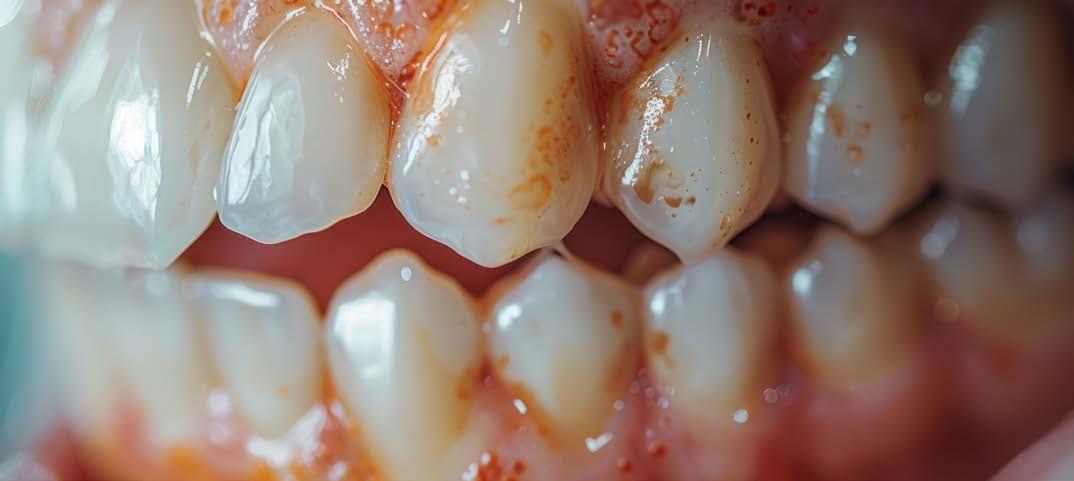

Estos hallazgos confirman el éxito del procedimiento quirúrgico y de la posterior carga progresiva, con un mantenimiento óptimo de los tejidos duros y blandos a lo largo de más de dos décadas (Figura 15). Los cambios entre el momento inicial y el final del tratamiento son evidentes, especialmente al comparar la imagen intraoral de la primera visita con la tomada a los 22 años, donde la mucosa que rodea al diente 21 —y posteriormente al implante— se muestra engrosada, en buen estado de salud y con una estética destacable. Asimismo, la comparación entre la radiografía inicial, que evidenciaba el fracaso del tratamiento de conductos del diente en posición 21, y la radiografía a los 22 años, que muestra el implante sin pérdidas óseas asociadas, resulta elocuente (Figuras 16 a 19).

Figuras 16 y 17. Comparación entre la imagen inicial —diente con cambio de coloración, encía inflamada y pérdida de grosor— y la obtenida a los 22 años, que muestra estabilidad y salud gingival con el implante.